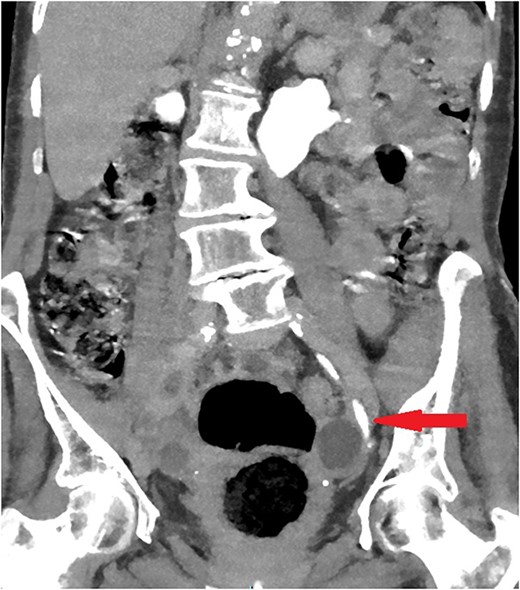

The old catheter was removed, and a replacement was inserted correctly into the bladder. The patient was managed conservatively with antibiotics. A further contrast CT was performed and showed mild extravasation of the contrast at the same level of the former catheter’s inflated balloon (Fig. 2). The patient improved clinically with conservative management, and her blood investigations remained stable. Follow-up contrast CT after 2 months was normal and showed no extravasation and no stricture (Fig. 3).

Coronal section of abdomen and pelvis contrast CT 24 h from the initial CT: The new urethral catheter balloon in the bladder (blue arrow). Contrast extravasates the left ureter at the site of the old catheter balloon (red arrow).